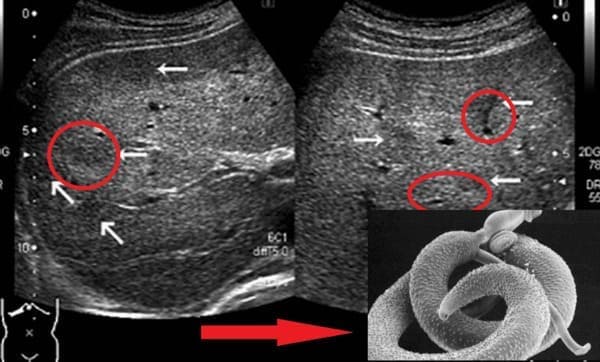

Egy újabb eset, ami még engem is megdöbbentett. Egy 49 éves beteg agyát teljesen ellepték a paraziták és azok lárvái. A halál oka - ischaemiás stroke volt. De ez csak következmény! A valóságban a paraziták egyszerűen emberi agyszövettel táplálkoztak és élve fogyasztották el! A beteg egész életében fejfájástól, alvás- és memóriazavaroktól szenvedett. Aztán, amikor elég nagy agyterületek sérültek, az epilepszia is hozzáadódott. Hat hónappal később meghalt.

Leggyakrabban a belekben kezdődik. A paraziták a szájon keresztül jutnak be a tápcsatornába, és problémát okoznak. Később más szervekbe is bejuthatnak, kiterjedt elváltozásokat okozva. Nézze meg az alábbi képeket.